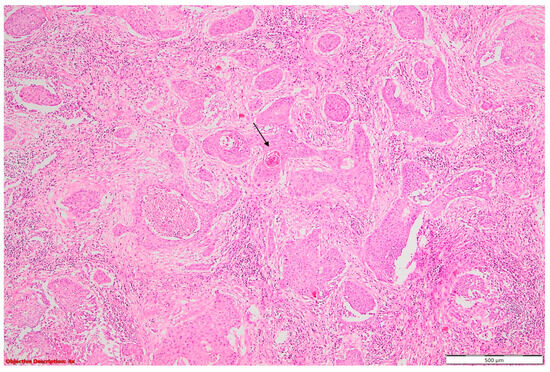

When examining the localization of coexisting lesions, a fascinating pattern emerged: a majority of cases (43%) showcased lesions within the same lobe (N = 16) (Figure 10). This intriguing observation raises questions about the accuracy of tumor staging, as lesions within the same lobe may suggest T3 tumor extension, potentially leading to misclassification and subsequent treatment decisions. Furthermore, 27% of cases exhibited lesions concurrently in both the same lobe and lymph nodes. This finding underscores the complexity of lesion distribution and highlights the need for meticulous nodal staging to accurately assess disease spread. In comparison, an additional 27% presented coexisting lesions spanning across different lobes (N = 10), posing challenges in determining the extent of tumor involvement and guiding surgical resection boundaries. Remarkably, only one case featured multiple lesions dispersed across distinct lung lobes and lymph nodes, underscoring the rarity and diagnostic dilemma posed by such multifocal presentations. These findings underscore the importance of the careful consideration of lesion localization in NSCLC staging to minimize staging errors, inform treatment decisions, and improve patient outcomes.

Figure 10. Coexisting lesions: lung carcinoma () and fibronodular lesion (→); HE, 40×.